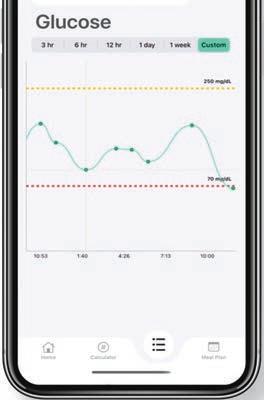

How teenager Jake Zur used his diabetes diagnosis to build an app that’s helping patients everywhere

When then-17-year-old Jake Zur was diagnosed with Type 1 diabetes in November 2020, something as simple as a Sunday morning doughnut stopped being a sweet treat and instead became something to be charted and analyzed. “I was managing my sugars on spreadsheets and making huge lists of everything I ate,” he recalls. “It just took way too long.”

Zur searched for a simpler solution, but none of the diabetes management tools he tried did the trick. So, the senior at The Benjamin School in Palm Beach Gardens decided to build his own app called SweetSpot–The Diabetes Manager.

Mixing technology with his diagnosis was a no-brainer for Zur, who plans to major in computer science in college and has spent a summer as a programming data analysis intern at Jupiter’s Max Planck Florida Institute for Neuroscience. It took him about four months to develop SweetSpot, but he used his tech know-how—plus some medical research, YouTube videos, and family support—to bring the app to life.

Available for free on the Apple App Store, SweetSpot offers a trio of functions: a carb calculator, a glucose log, and a meal planner.

Zur is hopeful the app will help other people with diabetes and says that getting it into the hands of those who really need it has been the sweetest part of the process. “I just want to get it out to [as many] people as possible,” he adds. “I’m always updating the app, trying to make it the best for users. The fact that I can possibly help other people learn to manage their diabetes with this app is great.”

He hopes others who are struggling with a diabetes diagnosis will be empowered to manage their blood sugars and to understand that it’s a learning process that takes practice. Sometimes they’ll be high and sometimes they’ll be low, but eventually, Zur says, they’ll find their sweet spot.